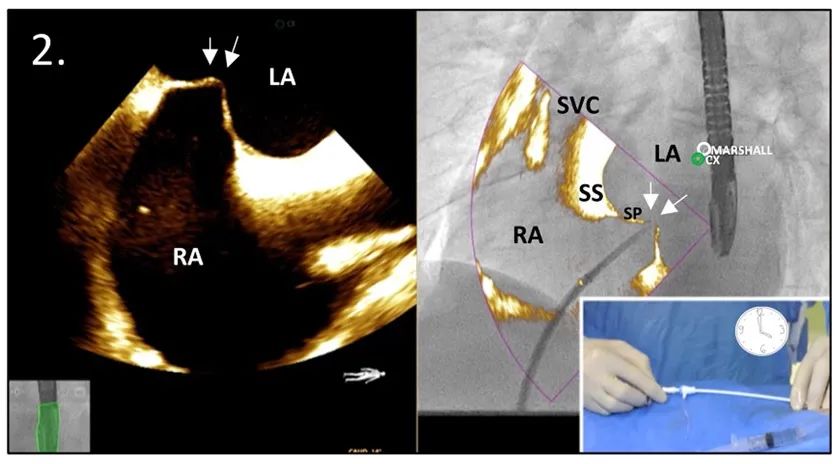

通过超声双腔切面和X-ray透视的叠加图像,可轻松获得经房间隔穿刺(TSP)位点。在标准的解剖学中,稍微左前斜(LAO)约30°投照可充分显示卵圆窝。通过简单地微调角度,转动X-ray透视使之与超声图像重合,以最佳方式打开和拉直卵圆窝。

图2:TSP的叠加图像:帐篷期(左)。注:穿刺针在4点钟方向(右下角图示)

缩写注释:Ao: 主动脉;CX,左回旋动脉;LA: 左心房;LAA: 左心耳;RA: 右心房;SP: 原发隔;SS: 继发隔;SVC: 上腔静脉;TEE: 经食管超声心动图;TSP: 经房间隔穿刺;白或黑色箭头,卵圆窝处的房间隔。